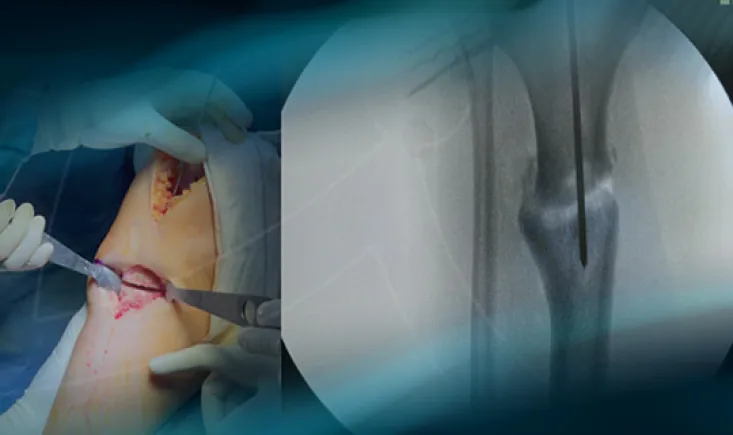

Discover step by step the minimally invasive posterior approach for hip replacement, which is muscle-sparin…